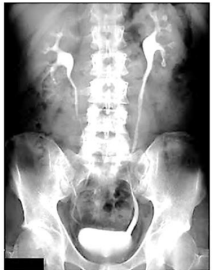

O exame fornece uma visualização panorâmica do

sistema coletor. Comumente são utilizadas incidências

oblíquas do abdome para melhor demonstrar os trajetos

ureterais, e uma radiografia pós-miccional que

demonstra se o esvaziamento vesical é adequado.

Observe a imagem e escolha a opção correta.